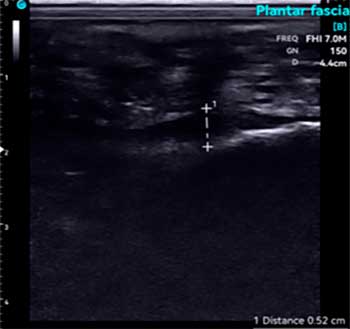

La utilización de un ecógrafo para diagnosticar la fasciosis plantar es esencial y es la herramienta más idónea para su examen.

En ecografía observamos una señal hipoecoica con separación de las fibras de la fascia plantar. El valor normal de fascia plantar sana es de 3mm. Es importante realizar un estudio ecográfico comparativo en el otro pie para visualizar el rango de grosor de la otra fascia.

A continuación adjunto varios casos de imágenes ecográficas con fasciopatía plantar: